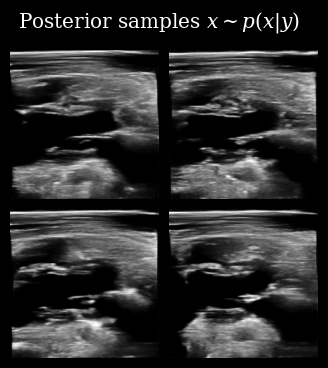

That looks correct, we now proceed with posterior sampling to generate some samples from the Bayesian posterior \(\{\mathbf{x}_t^{(i)}\}_{i=0}^{N_p} \sim p(X_t \mid \mathbf{y}_{<t})\).

[11]:

posterior_samples = diffusion_model.posterior_sample(

measurements=measurement_buffer,

mask=mask_buffer,

n_samples=n_particles,

n_steps=n_posterior_steps,

initial_step=0,

omega=10,

)

animate_samples(

posterior_samples[0],  # posterior samples has an extra batch dim of length measurements

"./task_based_posterior_samples.gif",

title=r"Posterior samples $x\sim p(x | y)$",

fps=9,

zea: Successfully saved GIF to -> task_based_posterior_samples.gif

Task Based Posterior Samples

Next we use these posterior samples to derive downstream task posterior samples, i.e. beliefs about the value of the LVID. We then compare this to the target LVID measured from the ground-truth in order to see how accurate the agent’s beliefs are.

We also plot this visually, quantifying our downstream uncertainty using Gaussian variance.